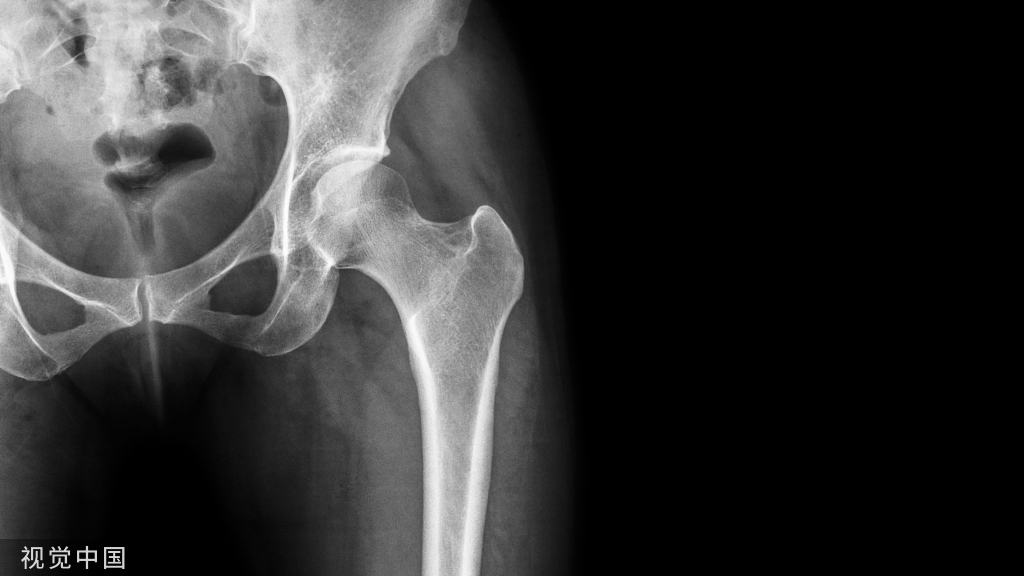

1、进钉点。髓内钉的位置在哪里最合适?

当然是髓腔的最中心,所以髓腔最中心的延长线就是最佳的进钉点。一般位于梨状窝。一个好的进针点可以保证力线,同时进钉后还有复位的作用,如果进钉点出现了偏移,可能整个手术都会有影响。好的开始象征着接下来手术的顺利,一定要取一个好的进针点。

他在正侧位的透视位置我们可以看到位于髓腔中心的延长线上

随着有外翻角的髓内钉的发明,我们现在目前用的可能多是大粗隆顶点进针的了

进针的角度,基本与股骨颈是垂直的角度